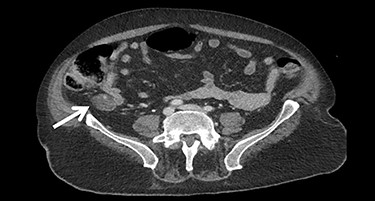

A gastroscopy showed a gastroparesis but no other pathologies. The next diagnostic step was a computed tomography (CT) scan, which showed a suspicious extraluminal mass in the right abdomen close to the terminal ileum (Fig. 1).

The gold standard for further diagnostics when suspecting a RFB is a CT. In case of RFB the CT scan can demonstrate a well-defined mass of mixed density with a thick peripherally rim enhancement, often calcified with a possible abscess formation. A ‘spongiform pattern’ is typical. The use of surgical sponges with radiopaque markers is highly recommended. On plain radiograph a curved or banded radiopaque line might be observed. Magnetic resonance imaging and other relevant radiological techniques may also be used depending on the clinical situation [1, 2].